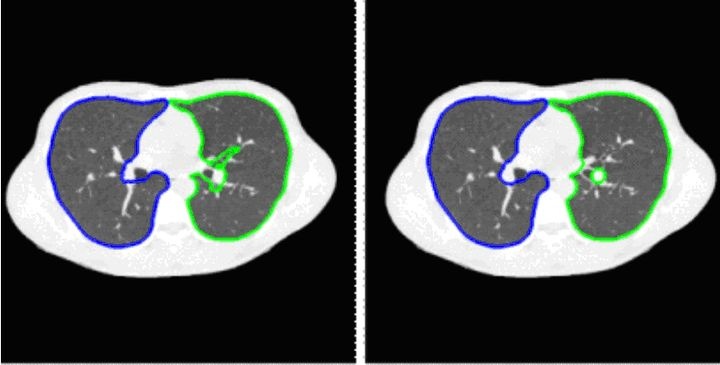

肺部CT图像分割结果

本图展示了肺部CT图像的分割结果。其中左侧区域是基于深度学习(DL)的网络分割成果,右侧区域则是人工分割的结果.通过对比可以看出,在医学图像处理方面基于深度学习的效果表现得非常接近人工处理的结果.